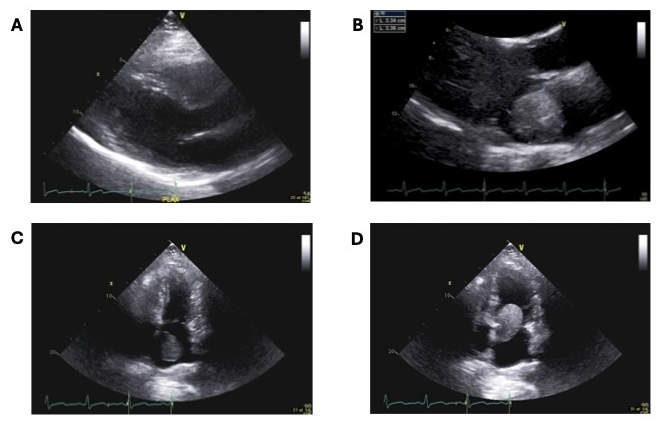

A 44-year-old female with a past medical history of unspecified skin cancer presented with exertional dyspnea for 1 day before admission and syncope 7 months before admission. Physical exam was noted for soft low low-pitched diastolic murmur at the cardiac apex, not appreciated on prior exam. Echocardiography revealed a 3.3x4.7 cm pedunculated, homogenous mass in the left atrium obstructing the mitral valve. Serum BNP was measured as 326. An echocardiogram from less than 29 months prior was reviewed and showed no mass in the left atrium. The patient underwent successful surgical resection of the mass. The mass measured approximately 7x6x2 cm. Histologic analysis reported a proliferation of myxoid stroma with cytologically bland spindle cells positive for calretinin, compatible with cardiac myxoma. Following the surgery, the patient experienced resolution of symptoms.

In this case, we present an unusually fast-growing myxoma in a woman with shortness of breath and syncope. The reported growth rate of atrial myxomas ranges from 1.3 to 6.9 mm a month. Our patient had a negative echocardiogram less than 2.5 years before her presentation, followed by the development of a 7 x 6 x 2 cm mass. Since the onset is unknown, the precise growth rate of our patient's tumor is unknown but was at least 24 mm/month. It is important to consider myxoma in the differential diagnosis of a woman with new onset murmur and syncopal episode. Furthermore, recognizing the potential for rapid expansion is crucial to assessing the risks versus benefits of myxoma section.